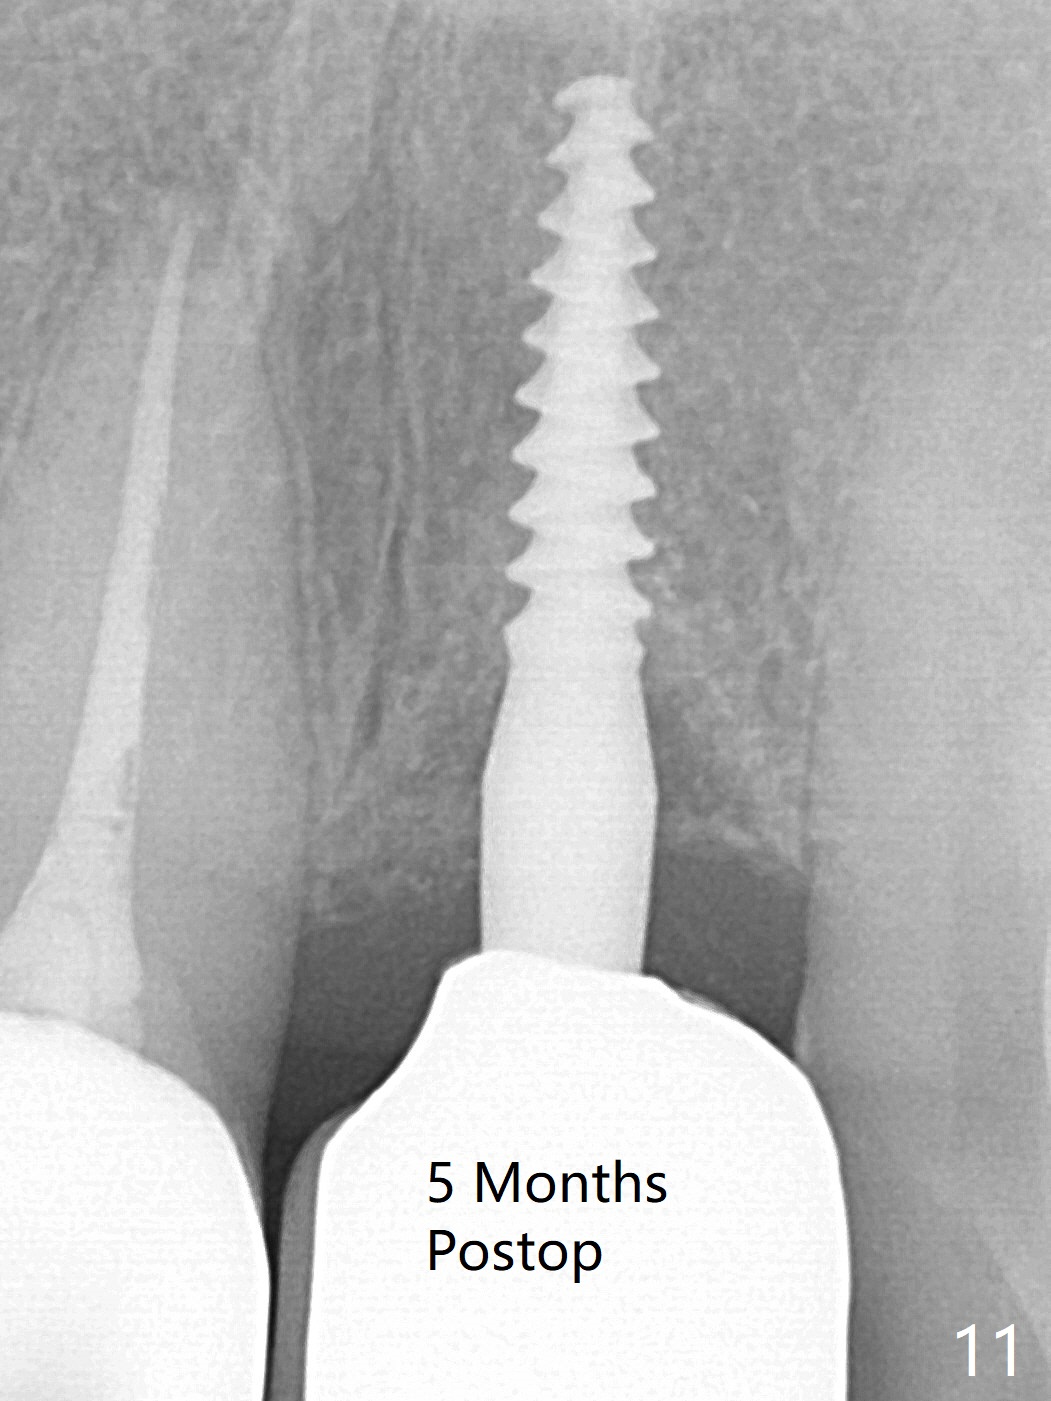

Three months postop there is no gross bone loss around the implant (Fig.10). It remains the same 5 months postop (immediately post cementation, Fig.11) and 3, 11 months post cementation (Fig.12,13).